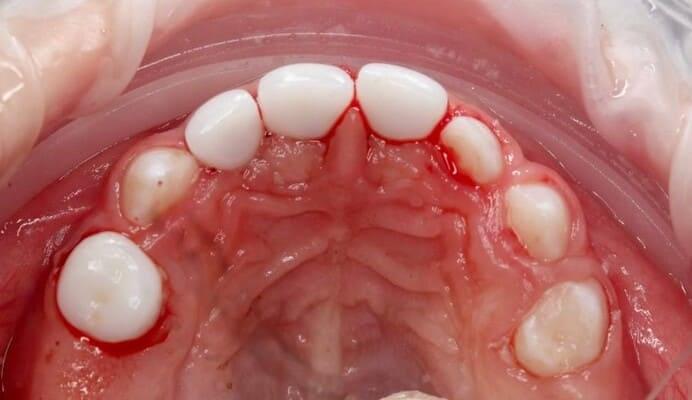

Пацієнт 2 років, уражено десять зубів, шість із яких потребують покриття коронками. В зв’язку зі значним об’ємом та складністю лікування прийнято рішення про лікування в умовах анестезіологічного забезпечення. Раніше була спроба пролікувати ці зуби застарілими методами, які не тільки не є ефективними відносно лікування, а ще і додають дитині комплексів через характерне фарбування зубів. Через високи естетичні вимоги дитини і батьків було прийнято рішення покривати естетичними цирконієвими коронками, як передні так і бічні зуби. Через 2,5 години дитина без інфекції в порожнині рота, з відновленим здоров’ям та естетикою посмішки може кусати, жувати, посміхатись без болю та дискомфорту. Останнє фото через 2 роки після лікування, оскільки естетичні коронки в дитячій стоматології - це надійність, естетика та функція.